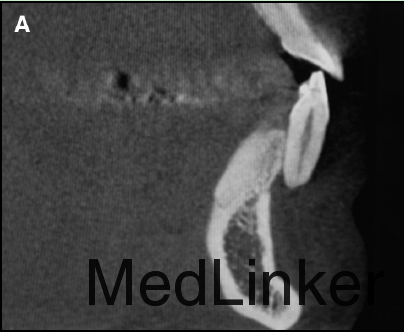

舌侧丝保持器在右侧侧切牙与尖牙间被破坏,右侧中切牙与侧切牙舌向移动,而左侧尖牙唇向移动。下颌运动过程中,左下2承受了切导的全部负荷。左下2活力测试显示无活力。CT矢状向显示32牙完全位于骨皮质外,32牙根尖1/3横断面显示牙根周围无骨质包绕